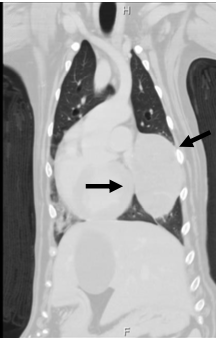

what is disseminated histiocytic sarcoma?

aka malignant histiocytosis

aggressive, with multiple sites of involvement

what are the anatomic predilection sites for disseminated histiocytic sarcoma?

-multi-organ

-LNs, liver, lung, spleen most common